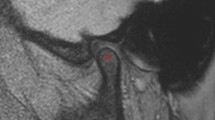

This retrospective study included 16 DM and age and sex matched 16 control patients (11 men, 5 women; mean age, 56.8 ± 14.4 years; range 31–78 years). Patients with Type I DM, prior history of taking bisphosphonates, osteoarthritis of the temporomandibular joint, and CT images with metal artifacts were excluded from this study. Bilateral mandibular condylar bone marrow was manually contoured on axial CT images. The presence or absence of DM is the primary predictor variable. Texture features of the region of interest was the outcome variable, that were analyzed using an open-access software, MaZda Ver.3.3. For each group, 20 features out of 279 parameters were selected with Fisher, probability of error and average correlation coefficient methods in MaZda. Bivariate statistics were computed with the Mann–Whitney U test and the P value was set at .05.